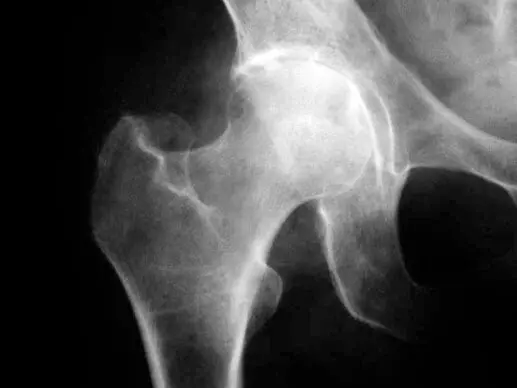

Згодом, якщо не зупинити розвиток артрозу, хрящ може повністю зникнути. Це відповідає 3-4 стадіям артрозу. Паралельно з’являються кісткові деформації в суглобі. Зменшення маси хряща разом з ущільненням кістки і появою кісткових деформацій називається остеоартроз (малюнок нижче).

Деформуючий артроз характеризується хронічним порушенням харчування хряща. Страждає також кістка, на якій розташований хрящ. Поступово хрящ зневоднюється, з’являються дефекти хряща, його висота знижується. На рентгені стає видно, як звужується суглобова щілина (на МРТ цього можна і не помітити). Втягується в процес кістка під хрящем, формуються кісткові розростання (Кразанн на мікрофотографії нижче: витончення суглобового хряща, суглобового відростка і формування остеофита при дислокаційному перевантаженні суглоба хребта (формування остеоартрозу).

При артрозі (остеортрозі) порушується функція суглоба, зменшується обсяг рухів в суглобі. Поступово розвиваються грубі деформації суглоба. Рухи стають болючими. Основний спосіб діагностики артрозу – це рентген суглоба. Важливими допоміжними методами оцінки стану суглоба і його тканин є УЗД і МРТ.